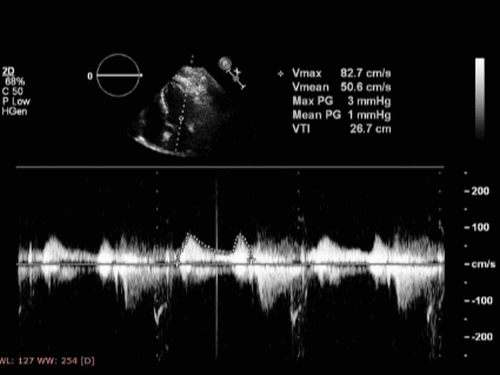

Площадь поперечного сечения отверстия митрального клапана составляет примерно 5,0 см2, что позволяет наполнению левого желудочка происходить преимущественно в раннюю диастолу (примерно две трети объема поступающей крови) с максимальной скоростью по эхокардиографии 50–100 см/с. Оставшаяся треть ударного объема проходит через митральный клапан во время систолы предсердий. Во время диастаза объем желудочков остается неизменным. При упражнениях и увеличении частоты сердечных сокращений диастаз укорачивается, а компоненты раннего и позднего наполнения сближаются, пока они не объединятся и не станут неразличимы на допплерографии. С возрастом картина наполнения меняется на противоположную, и доминирующее наполнение левого желудочка происходит в позднюю диастолу.

- Падение давления на митральном клапане: Используя модифицированное уравнение Бернулли (4 V2), можно измерить максимальное и минимальное падение митрального давления и рассчитать среднее значение.

- Время полуспада градиента давления: это время, за которое раннее диастолическое трансмитральное давление падает до 1/2 своего пикового значения (или время, необходимое для начальной скорости, деленной на квадратный корень из 2, который равен 1,4). Затем рассчитывается митральная площадь как константа (220), деленная на давление 1/2 времени. Хотя установлено, что митральное давление 1/2 времени коррелирует с инвазивным измерением площади митрального клапана, оно также имеет серьезные ограничения, особенно у пациентов с фибрилляцией предсердий и высокой частотой сердечных сокращений. Кроме того, давление 1/2 времени зависит от сопротивления притоку левого желудочка из-за формы воронки митрального аппарата, включая компоненты как отверстия, так и состояния подклапанного аппарата. Повышенное сопротивление подклапанных структур может замедлить падение давления в приточном тракте, так что давление 1/2 времени обычно меньше, чем полученное с помощью 2D планиметрии. Противоположное явление наблюдается у пациентов с сопутствующей регургитацией на аортальном клапане или с гипертрофией левого желудочка, когда давление в 1/2 раза превышает степень митрального стеноза. Следовательно, после митральной вальвулопластики расчет может давать недостоверные значения. Основная причина недооценки точности этого метода заключается в том, что он основан на падении давления, которое часто не является экспоненциальным.